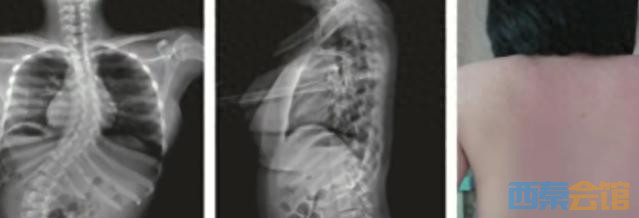

近日,江苏13岁女孩欣欣在练习舞蹈的下腰动作时,不慎受伤导致瘫痪。

南京鼓楼医院脊柱外科行政主任朱泽章介绍,事发时,欣欣在完成下腰动作的瞬间听到“咔嚓”一声,随后向父母和老师反映腰痛、腿麻。遗憾的是,这种损伤一旦发生,往往无法逆转。

“瘫痪之后,孩子只能依靠轮椅生活,久而久之,脊柱也会出现弯曲。”朱泽章表示,不仅双手生活能力受限,心肺等多个脏器功能也因脊柱变形受到压迫。无奈之下,父母将她送到南京某医院脊柱外科就诊,进行微创矫形治疗。

医生指出,像欣欣这样,因为下腰导致瘫痪的病例几乎每年都会出现。他提醒:跳舞时一定要小心,做下腰动作一定要循序渐进,并做好热身、预备动作等。

此外,医生也提醒,孩子在练习舞蹈动作时,一定要接受正规专业的指导,一些特殊运动或者动作非必要不去尝试。